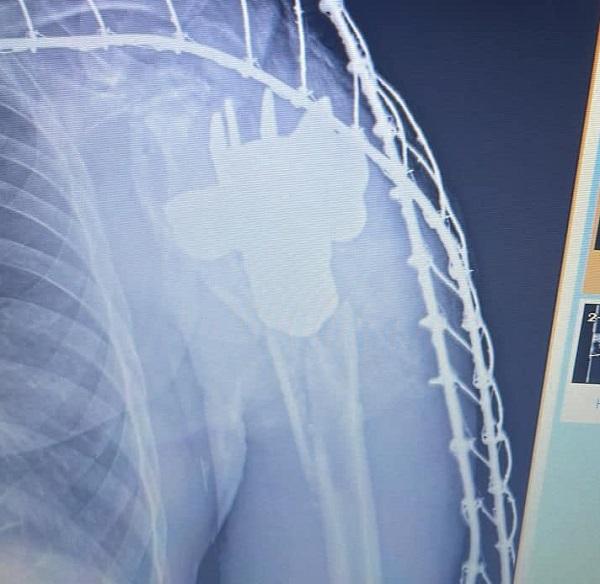

Так, під час дообстеження медики одного з прифронтових шпиталів виявили у тілі пораненого невідомий сторонній предмет, контури якого нагадували хвостовик міни, повідомляє командування Медичних сил ЗСУ.

Лікарі викликали на місце бригаду саперів. Фахівці зробили висновок, що предмет можна видалити безпечно.

"Після дослідження, лікарями було прийнято рішення про оперативне втручання та видалення хвостовика, який ви бачите зараз на фото", - розповіли подробиці у у командуванні, опублікувавши фото хвостовика у пів долоні завбільшки.

За даними лікарів, наразі поранений військовослужбовець перебуває у стабільному стані та готується до подальшої медичної евакуації та реабілітації.